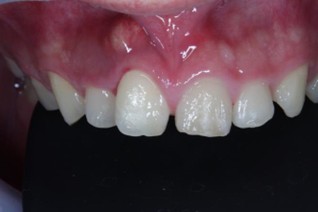

20代 男性

治療後

治療後- リスク・副作用

- 20代/男性

- 患者の具体的な症状

- 1年前に左上12 右上1の根の治療をし、その後放置していたら、左上2が破折した。

左上2インプラント補綴 左上1右上1オールセラミック装着。

歯根破折と虫歯による痛み、審美障害を主訴として来院。 - 検査方法

- コーンビームCT、レントゲン撮影

- 診断結果

- 左上2 歯根破折

- 治療詳細

- 左上抜歯後、インプラント埋入1本

骨造成あり 局所麻酔

インプラント治療後、左上1右上1セラミック修復2本 - 通院回数

- 9回

- 治療期間

- 12か月